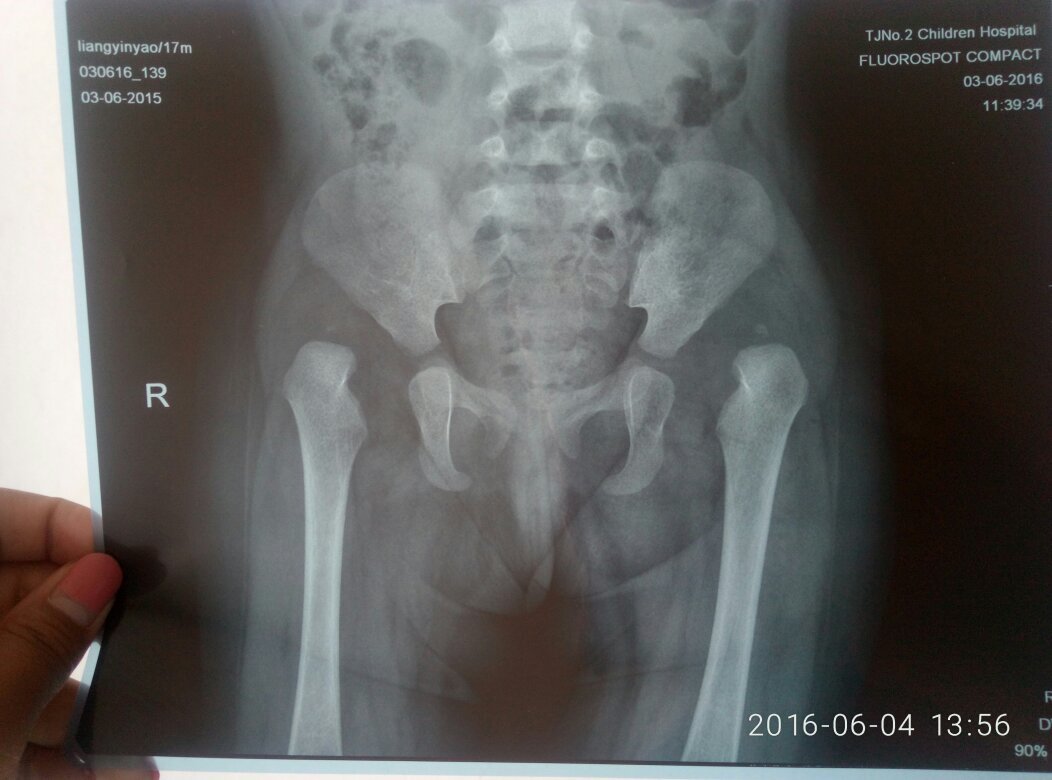

女宝17月龄,患有双侧先天性髋关节脱位,不知道去哪个医院治疗好一点,要花多少钱,老家是河北廊坊霸州 女宝17月龄,患有双侧先天性髋关节脱位,不知道去哪个医院治疗好一点,要花多少钱,老家是河北廊坊霸州同上 点击展开 匿名用户 2016-06-04 14:31 满意回答 最好听听你现在医生的意见 匿名用户 2016-06-04 17:35 宝宝知道提示您:回答为网友贡献,仅供参考。 为您推荐: 其他回答 还是去北京儿童医院或者301医院,先好好打听一下吧。 匿名用户 2016-06-04 14:35 郑州 凤凰知传奇 2016-06-04 14:32 相关问题 在廊坊或霸州市怀孕五个月做引产的费用 廊坊第四医院顺产要花多少钱啊? 廊坊第四医院剖腹产要花多少钱啊?